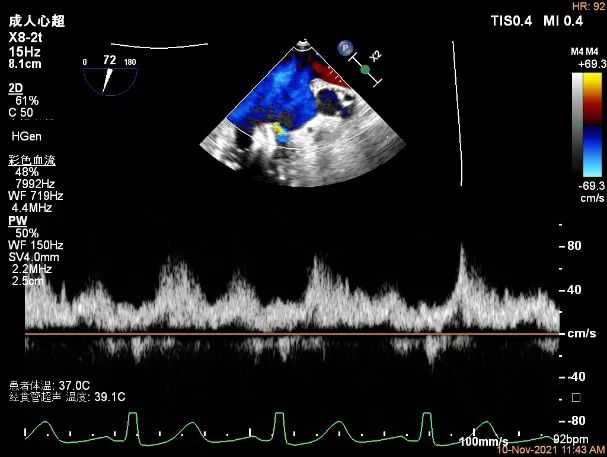

Bicom:MR(重度),反流束宽9.6mm,反流面积15.7cm²

PISA法定量EROA:1.05cm²,Rvol:148ml,RF:58%。

肺静脉血流频谱呈收缩期反向

二尖瓣口平均跨瓣压差:6mmHg

TEE Bicom view:主要病变区域为P1区,瓣叶中部可见连续性中断